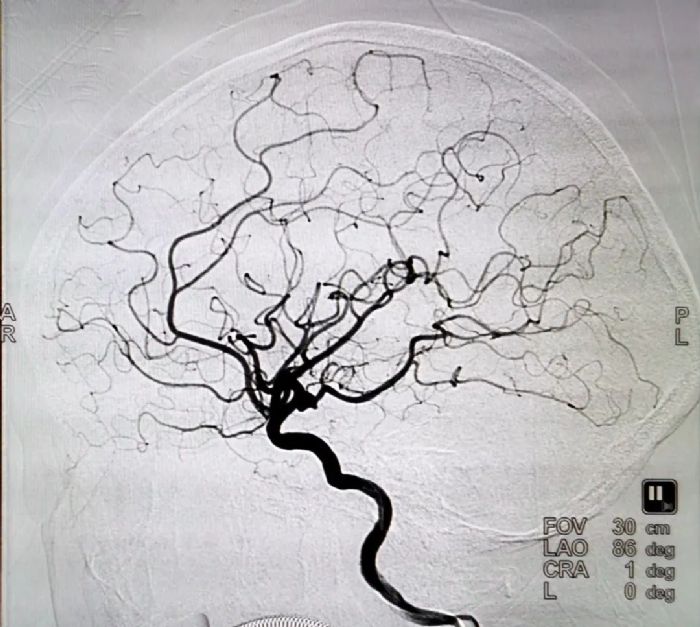

7月26日,在中南大学湘雅医院神经外科沈沉浮主任的指导下,绥宁县人民医院圆满完成县内首例经股动脉穿刺全脑动脉造影+颅内动脉瘤栓塞术,该手术难度为四级(最高等级),标志着我院在脑血管疾病治疗又迈上了一个新的台阶。 患者女性,54岁,因突发头痛4小时入院。入院查体:神志清楚,四肢肌力肌张力基本正常。经头部CTA诊断为蛛网膜下腔出血、左侧颈内动脉后交通段动脉瘤。 颅内动脉瘤被神经外科医生称为颅内的“定时炸弹”,由于其破裂后的死亡率极高,介入治疗颅内动脉瘤是一项对技术和材料要求极高的微创手术,创伤小、恢复快,是目前治疗颅内动脉瘤的重要手段,这种争分夺秒的手术不允许术者有毫厘差错,术者必须要有足够的自信和心理承受能力。 脑卒中起病急,病情凶险,时间就是大脑,时间就是生命。专家团队得知其病情后,为患者做了详尽的检查后确定可以可以进行该类介入手术,并制定了周密的手术计划。 术前VS术后 绥宁县人民医院神经外科黄敏主任、大外科党支部书记、麻醉科主任陆居兵,放射科苏增武医师、麻醉科颜志鹏医师在中南大学湘雅医院神经外科沈沉浮主任的指导下,予患者在全麻下经右侧股动脉穿刺,造影后可见左侧颈内动脉末端有大小约3*4*3mm动脉瘤,选取合适角度路径图引导下,取支架导管在微导丝引导下,将微导管头送入动脉瘤内,退出微导丝,经微导管填入4枚弹簧圈,造影显示稳定,动脉瘤已致密填塞,再将支架完全释放;将6F导管退出到达左颈总动脉分叉下段进行造影,见左侧大脑前、中、后及脉络膜前显影良好,无动脉夹层,退出导管后,压迫止血,包扎伤口。术毕,手术顺利,术中出血约10ml,患者安返ICU。 这是绥宁县人民医院介入治疗的又一创举,这一技术的的成功开展应用,为今后进一步开展脑血管病介入手术治疗奠定了基石,让脑血管疾病的患者有了更多的治疗选择,真正实现了“大病不出县” 的医改目标和要求。 |